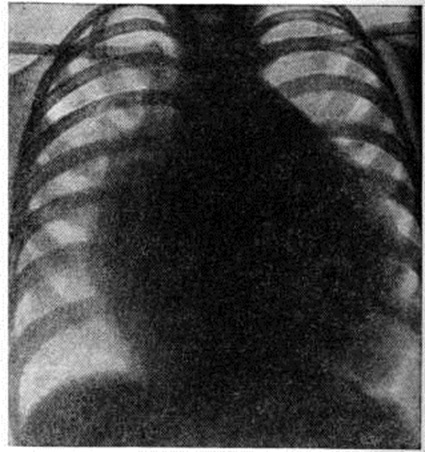

Рентгенограмма грудной клетки больного при полной форме атриовентрикулярного канала (прямая проекция): контуры сердца округлой формы за счёт увеличения правых и левых отделов.

Определяемое расщепление II тона с усилением лёгочного компонента связано с гиперволемией малого круга и блокадой правой ножки пучка Гиса. На ЭКГ — отклонение электрической оси сердца влево. На ФКГ над верхушкой сердца и в четвёртом межреберье слева регистрируется интенсивный систолический шум, связанный с регургитацией крови из желудочков и сбросом крови из левого желудочка в правый. Эхокардиограмма регистрирует необычные движения передней створки митрального клапана, иногда её расщепление и наличие промежутка между ней и межжелудочковой перегородкой. Рентгенологически определяется умеренная или значительная кардиомегалия и дилатация лёгочного ствола (рисунок 7).